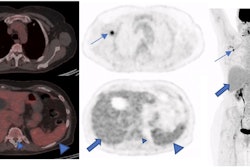

A 49-year-old patient with primary clinical stage III melanoma underwent F-18 FDG-PET. The primary tumor Breslow thickness was 6.5 mm. On initial F-18 FDG-PET images, this patient had a high SUVmax (52), resulting in limited survival with the occurrence of brain metastasis in the first year of follow-up (horizontal arrow). Notably, during the course of the treatment, the patient underwent surgical removal of the primary tumor as well as lymph node dissection, followed by neoadjuvant radiotherapy and immunotherapy. Image courtesy of Cancers.